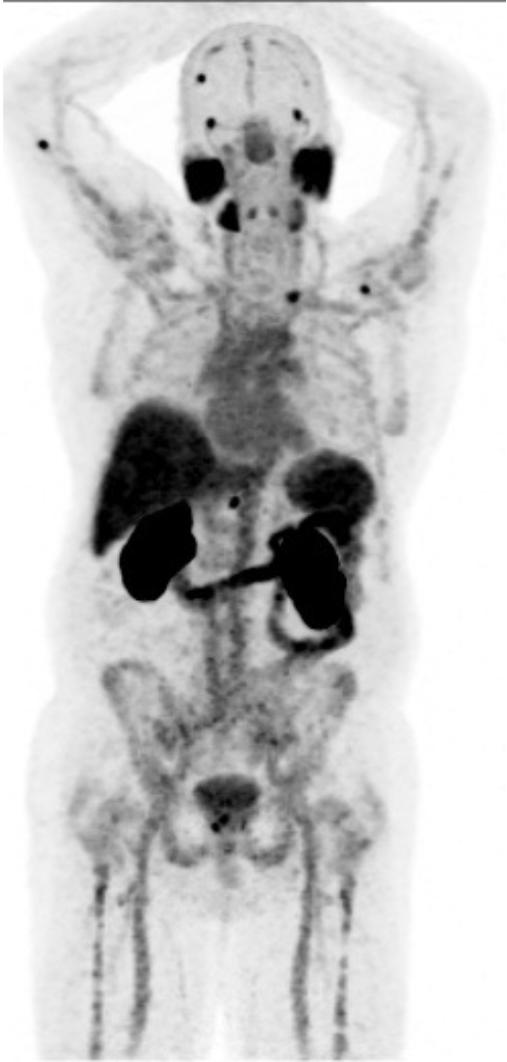

Le foie, les reins, la rate, les glandes salivaires et lacrymales, le duodénum et l’intestin grêle ainsi que la vessie sont des structures normalement visualisées lors d’un TEP au Ga68-PSMA. (Figure 2)

Aux figures 3 et 4, nous pouvons voir le même patient en TEP Ga68-PSMA et TEP F18-FDG avant le début des traitements. Sur la figure 5, nous avons le même patient environ 3 mois après la fin de ses 6 cycles de traitements.